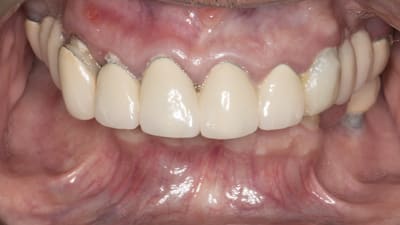

Kois Center Case Occlusion Correcting Occlusal Dysfunction While Addressing Patient’s Esthetic Concerns By Jennifer Graas, BMSc September 01, 2022 13 min read